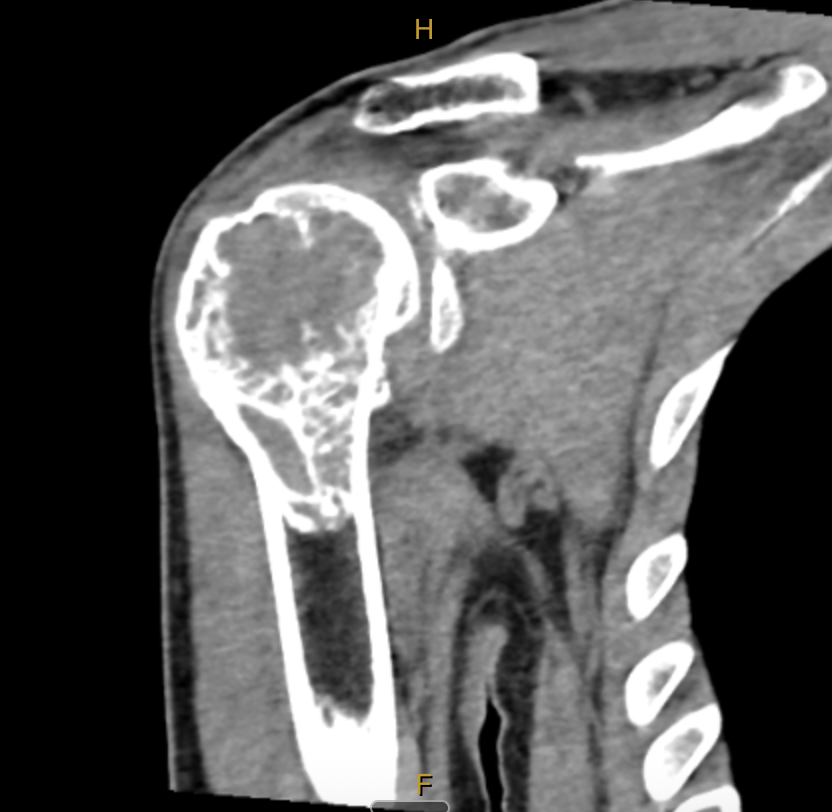

MRI scan showing giant cell tumour in the right proximal humerus

MRI at diagnosis

Within days of that diagnosis, my wife Katie and I packed up and moved to Melbourne. In January 2022, I met my first surgeon. The clinical picture was confronting: the tumour was large, it had destroyed significant bone stock, and the surgical margins were going to be tight.

The plan was to start denosumab, a monoclonal antibody that targets RANKL, the key driver of the giant cells that give the tumour its name. The idea was that denosumab could help regrow bone stock, improve the surgical margins, and give us a better shot at limb salvage rather than going straight to a total reverse shoulder replacement.

I did six doses, the standard loading protocol. The bone stock improved. But the margins were still insufficient for limb salvage surgery. And the recommendation from my surgeon was clear: we should go to reverse shoulder replacement.